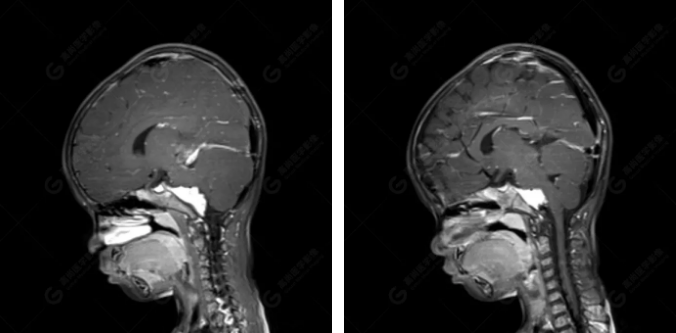

右側(cè)顳葉腫瘤切除術(shù)后(具體不詳):右側(cè)顳部骨質(zhì)不連續(xù)呈術(shù)后改變,右側(cè)顳葉術(shù)區(qū)見(jiàn)片狀長(zhǎng)T1長(zhǎng)T2信號(hào)影,F(xiàn)LAIR呈低信號(hào);術(shù)區(qū)后方右側(cè)顳枕葉見(jiàn)一巨大占位性病變影,邊界欠清,大小約6.2×5.8×4.3cm(前后×左右×上下),信號(hào)不均勻,T1WI呈等稍低信號(hào)間雜少許高信號(hào),T2WI呈高稍低混雜信號(hào),DWI示部分病灶彌散受限,相應(yīng)ADC圖減低,磁敏感序列見(jiàn)部分呈極低信號(hào),增強(qiáng)掃描可見(jiàn)明顯不均勻強(qiáng)化,鄰近硬腦膜及小腦幕增厚并明顯強(qiáng)化;另延髓右前方及右側(cè)橋小腦角區(qū)見(jiàn)一不規(guī)則形異常信號(hào)影,大小約3.2×1.3×3.7cm(左右×前后×上下),呈長(zhǎng)T1稍長(zhǎng)T2信號(hào),F(xiàn)LAIR呈等信號(hào),DWI未見(jiàn)受限,增強(qiáng)后明顯均勻強(qiáng)化,鄰近腦膜明顯強(qiáng)化。鄰近腦實(shí)質(zhì)及右側(cè)顳角明顯受壓;左側(cè)大腦半球未見(jiàn)局灶性信號(hào)異常,中線結(jié)構(gòu)稍左移。

右側(cè)顳葉腫瘤切除術(shù)后:現(xiàn)術(shù)區(qū)后方右側(cè)顳枕葉及延髓右前方占位,右側(cè)顳枕部硬腦膜及小腦幕明顯強(qiáng)化,結(jié)合既往影像資料,考慮為胚胎源性惡性腫瘤,如非典型畸胎樣/橫紋肌樣瘤(AT/RT)或原始神經(jīng)外胚層腫瘤(PNET)。